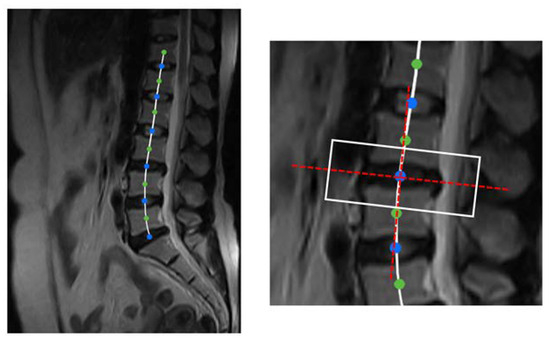

Figure 5 is the curve-fitting diagram of the spine. The rectangular frame is intercepted according to the normal and tangent of the spine fitting curve at the key points to ensure that the mask can completely cover the disc and the vertebra and that the direction is level with the mask.

Ref. [40] focused on the morphological analysis and feature recognition of the herniated intervertebral disc during the classification and geometric diagnosis of intervertebral disc herniation (HIVD). It shows that the diagnosis of degenerative disc disease is inseparable from the discrimination of disc herniation. In order to ensure that the model is not disturbed by unnecessary features, the features are located in the area of the intervertebral disc protrusion. According to [41], disc diseases are mainly characterized by the circumference in the axial section. For example, bulging is defined as asymmetric if it is more evident in one section of the periphery of the disc but is not so focal as to be characterized as a protrusion. In our dataset, it can be found that the intervertebral disc protrusion is primarily located in the middle of the lower portion of the axial section image. Based on this, we suppose the height of the axial image is h and the width is w, and take ( 9 / 14 × h , 1 / 2 × w ) as the center point and intercept a rectangular box with a height and width ratio of 1:1.5. Suppose the height of the sagittal image is H and the width is W. Take the key point as the center and divide it according to the ratio of height to width of 1:3. The width is 50 / 512 × W and the height is 150 / 512 × H . The axial image and the sagittal slice at the interception are spliced up and down, and the width and height are unified to 224 × 224 to obtain a multi-angle view of the disc. Figure 7 shows the splicing process of the multi-angle view of the disc.

Figure 5. Spine curve fitting and section cutting. (Left) A smooth spine curve was obtained by fitting the spine curve using the quadratic spline difference method. (Right) A rectangular slice of size (50/521*W, 150/521*H) is cut along the tangent direction of the fitted curve.